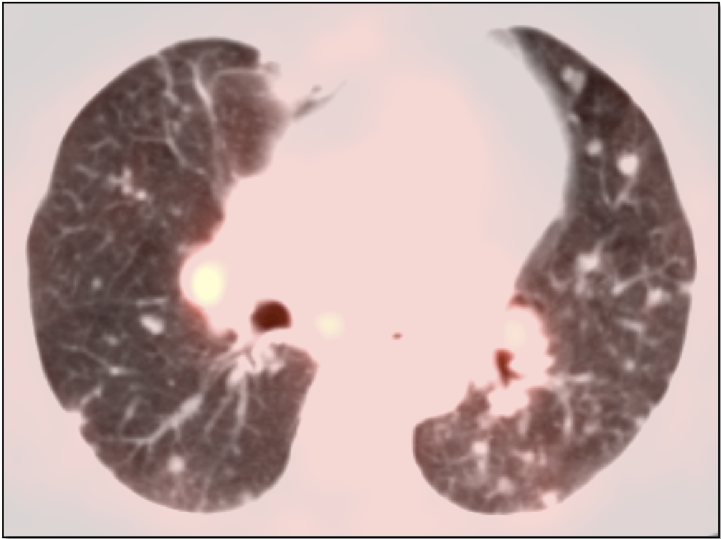

• Hematogenous spread, often to lungs, bone, liver, and brain.

Metastatic Disease: Metastatic RCCA lesions are usually more FDG avid than the primary lesion (nearly all demonstrate metabolic activity greater than liver uptake).

• PET/CT has high much higher sensitivity for metastatic lesions than for the primary lesion.

Primary Lesion:  Because many primary RCCA lesions are only mildly FDG avid, we must raise a suspicion of RCCA for any FDG-avid renal lesion (cystic or solid) — unless we can clearly characterize it as a fat-containing angiomyelolipoma.